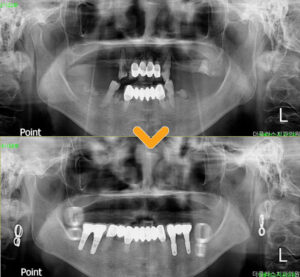

조금 더 정밀한 진단을 위해

파노라마 사진을 촬영해 보았더니

곳곳에 잔존 치근이 남아있었고

특히 상악에는 치아가 뿌리까지

충치에 이환되어 발치가 필요하였으며,

나머지 치아들도 치근이 짧아지고

치조골이 퇴축되어 흔들림이

심한 상태라 발치가 진행되어야 했습니다.

임플란트를 먼저 식립하여 유착 과정을

기다리는 동안 틀니를 완성시킨 후

위아래 교합을 맞추어

치료를 진행하기로 하였습니다.

먼저 하악의 잔존 치근들과

좌측 소구치 하나를 발치한 후

임플란트 식립을 진행하였으며,

치조골의 양이 부족한 부분에는 픽스쳐가

단단히 고정될 수 있도록

치조골 이식을 함께 진행하여

4개의 임플란트를 식립하였습니다.